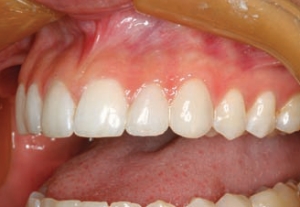

Figure 18--An unretracted smile view after completion of tooth number 9.

Patient J. R., aged 19 years, attended the dental office with a chief complaint of a failing upper right central incisor. He was seeking a second opinion regarding his options for replacing the tooth. He was excited by the option of immediate implant placement and provisionalization because his appearance during the healing interval was a … Read more